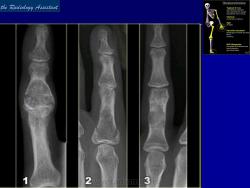

Энхондрома (син.: хондрома, центральная хондрома) — доброкачественная хрящевая опухоль, расположенная в костномозговом канале (интрамедуллярно). Встречается в 10 % случаев от общего числа доброкачественных опухолей костей. Считается, что она возникает из эктопически расположенных островков хряща, отщепившегося от пластинки роста на ранних этапах онтогенеза. В ряде случаев опухоль остается бессимптомной и обнаруживается случайно при рентгенологическом исследовании. В других случаях возникают боль и припухлость. Обычно болезненными становятся все энхондромы фаланг. Наиболее частая локализация: фаланги, главным образом, пальцев кистей, проксимальный конец плечевой кости, проксимальный или дистальный концы бедренной кости. При рентгенологическом исследовании в энхондроме определяются просветления с участками минерализации. Тень кости становится более широкой, кортикальный слой сохраняет целостность, но истончается. В редких случаях энхондрома имеет вид эксцентрически растущего экзофитного новообразования. Макроскопически опухоль представляет собой голубовато-белую полупрозрачную хрящевую ткань, в которую вкраплены желтоватые участки обызвествления. Опухоль состоит из отдельных хрящевых узелков, диаметр которых варьирует в пределах 1 см.

Рентгенологическая картина хондромы представляет четко очерченный опухолевый узел. Очаги минерализации в хондромах выглядят достаточно характерно и представлены очаговыми, глыбчатыми или кольцевидными , арочными отложениями извести. Полного разрушения кортикального слоя трубчатой кости с выходом опухолевых масс в мягкие ткани не наблюдается.